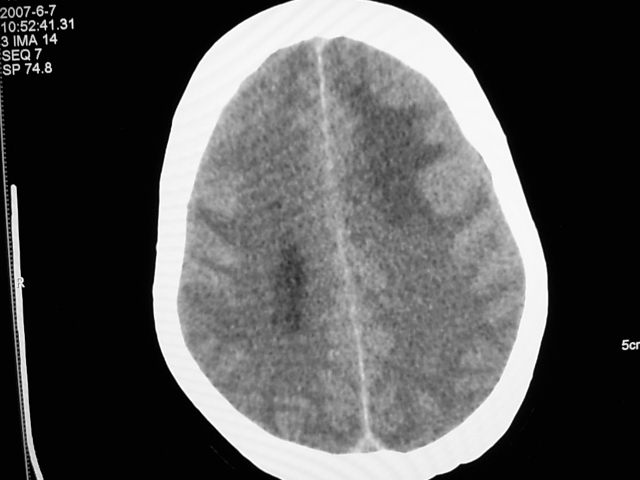

患者 女 63岁,近几周感觉头部不适来查体。

请调骨窗。多考虑前中颅窝脑外肿瘤,脑膜瘤、淋巴瘤或血管外皮瘤均有可能,蝶嵴脑膜瘤可能性最大。

左侧额颞部巨大肿块,平扫呈略高密度,增强明显强化,周围水肿明显,左侧侧脑室受压,右侧侧脑室扩大,中线明显右移,局部骨质增厚,支持脑膜瘤、大脑廉下疝。